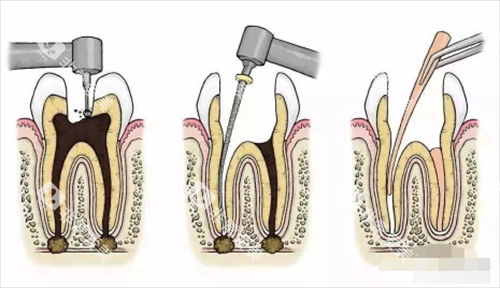

这根管治疗一般分这么几个步骤。首先是检查和诊断,医生得看看牙齿到底啥情况,确定是不是得做根管治疗。然后就是局部麻醉,毕竟这治疗过程可能会有点疼,打了麻药能让孩子好受点。接着就是打开牙髓腔,把里面坏死的牙髓清理出来,再用专门的工具把根管扩大、消毒。然后一步就是把根管填充好,再把牙齿补起来。

根管治疗到底是个啥呢?简单来说,它就是当牙齿的牙髓出了问题,像被细菌感染啦,或者牙髓已经坏死了,医生就会把牙齿里面的牙髓清理干净,再把根管填充起来,这样能防止感染进一步扩散,保住牙齿。